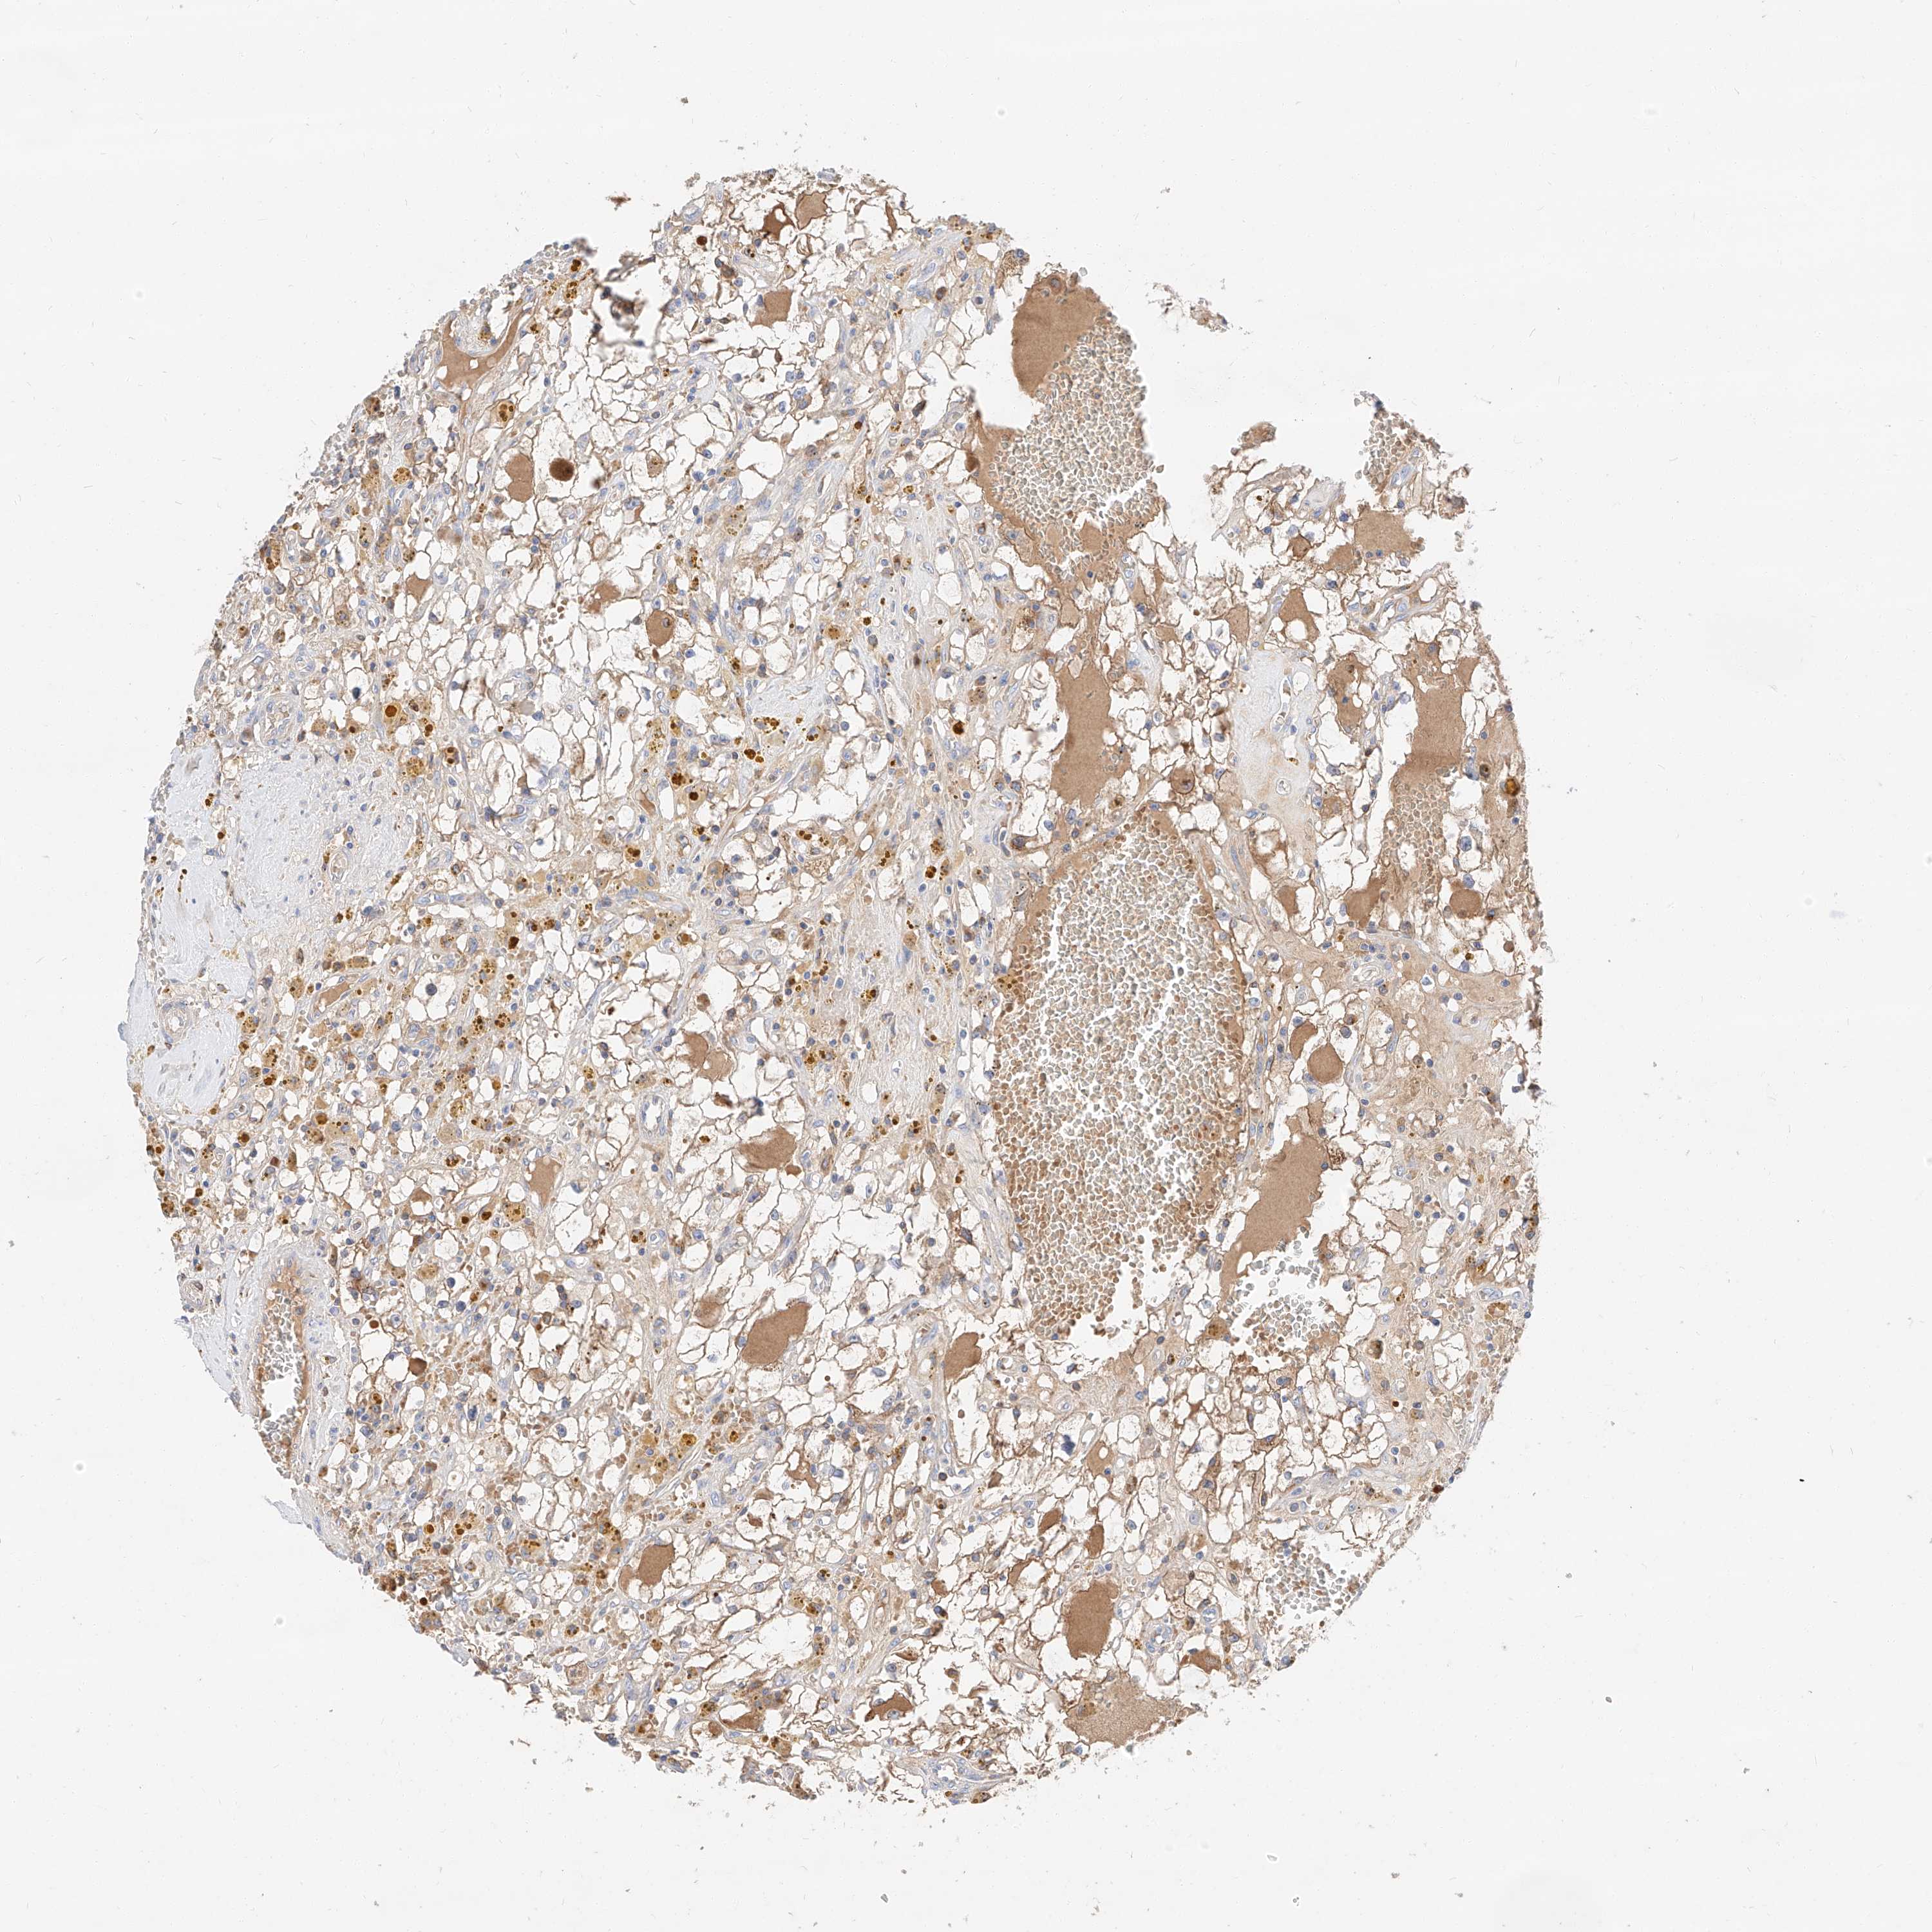

CANCER RENAL CANCER Show tissue menu

KICH TCGA KIRC TCGA KIRC VALIDATION KIRP TCGA PROTEIN RCC CPTAC PROTEIN EXPRESSION